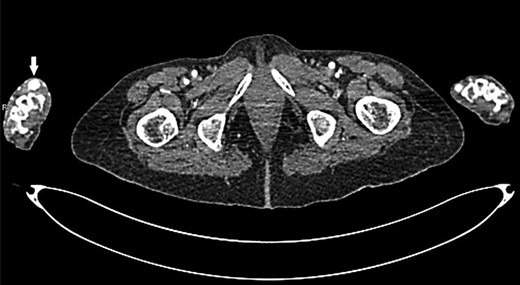

Upon physical examination, a mass of 2-by-3 cm found at the anatomical snuffbox area of the right hand, with no visible scars (Fig. 1). The mass was pulsatile, and no bruit was detected. The examination of the other arteries was negative. Later, CT angiography detected a local dilation at the distal part of the right radial artery (Figs 2 and 3). Complete body scan showed another aneurysm at the right common iliac artery measured 3-by-2.8 cm for which the patient was referred to a higher centre for possible endo-vascular intervention as it is not available in our hospital.

Transverse section of CT angiogram shows radial artery aneurysm at right hand (arrow).